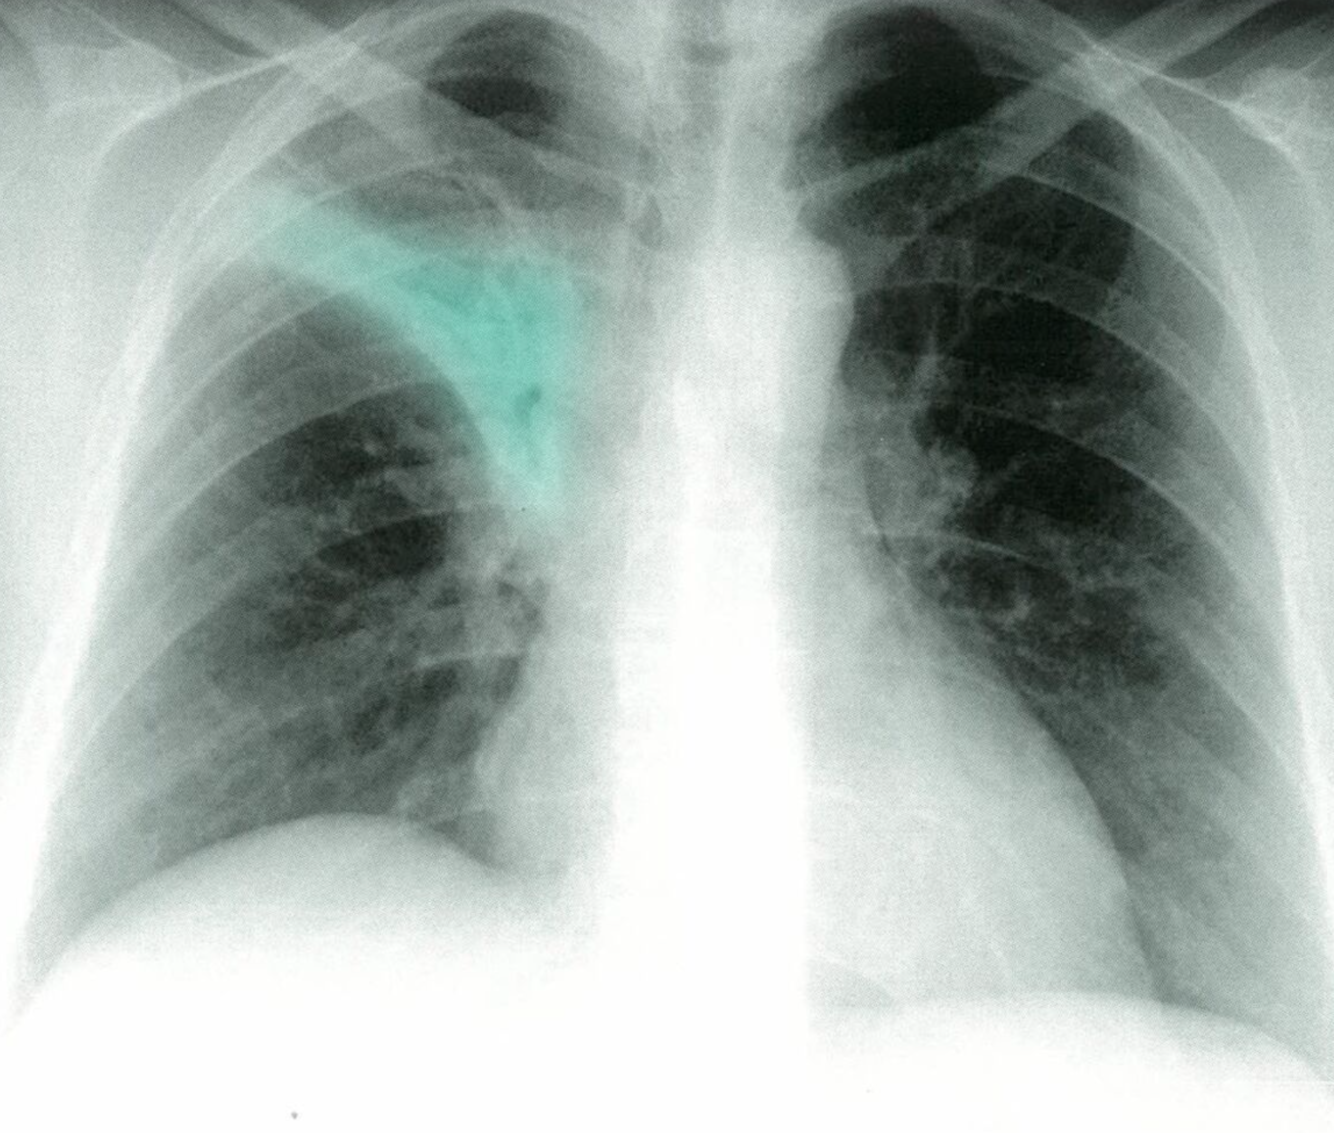

Post-primary tuberculosis

Posteroanterior chest x-ray showing bilateral apical, streaky parenchymal densities (green borders). These are most likely cavernous changes, which may occur during the course of post-primary tuberculosis. The full extent of cavernous formation can not be assessed on an x-ray; a CT scan should be performed.